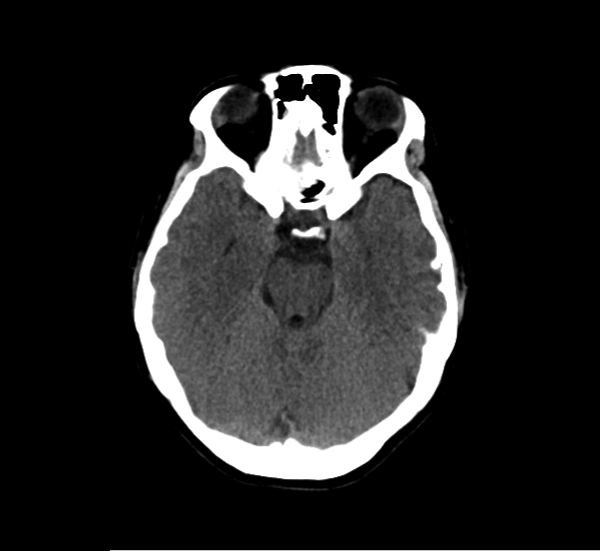

CT Brain Anatomy